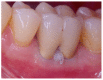

Various classification systems have been proposed to describe furcation lesions and Glickman's classification for many years seems to have been the most widely utilized in the sole clinical diagnosis with no reference to the prognostic value of the lesion itself. This article reviews the previous classification systems and proposes a new method to classify furcation lesions based on the position of the gingival margin and its relationship with the furcation area (clinically exposed/non-exposed furcation area) providing significant aid for a better understanding of furcation involvements and increases the prognostic value of treatments in the long term.